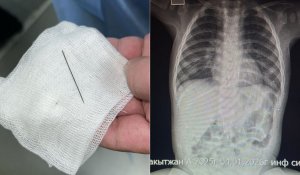

Оқиға жайлы ақпарат алғашында sadaqmedia сайытнда тараған. Порталдың хабарлауынша, Жетісу облысының Сарыөзек ауылында 19 жастағы әскери қызметшіге оқ тиіп, ауруханаға түскен. Оқиға 2 қыркүйек күні болған. Аталған факт бойынша қылмыстық іс қозғалды. Оқ тиіп жараланған әскери қызметкер – Темірбек Мыңжасаров. 19 жастағы кіші сержант Сарыөзек гарнизонындағы әскери бөлімде жұмыс істеген.

Әскери қызметшінің әкесі оқ тиген ұлын бастықтары ауруханаға апармай, пәтерде тығып ұстаған айтып шағымданған.

«2024 жылғы 2 қыркүйекте Сарыөзек гарнизонындағы 12740 әскери бөлімінің келісімшарт бойынша әскери қызметшісі қару-жарақты қолдану ережелерін бұзудың салдарынан оң қолынан жарақат алды. Әскери қызметші Талдықорған қаласындағы облыстық ауруханаға жатқызылып, оған барлық қажетті медициналық көмек көрсетілді. Зардап шегушінің денсаулық жағдайы қанағаттанарлық. Аталған факті бойынша қылмыстық іс қозғалды. Тергеу мүддесі үшін өзге де ақпарат жариялауға жатпайды», - делінген түсініктемеде.